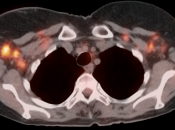

Metastatic Disease:

- Direct invasion of adjacent structures.

- Lymphatic spread to pelvic and retroperitoneal lymph nodes.

- Hematogenous spread, often to lungs, liver, and bone.